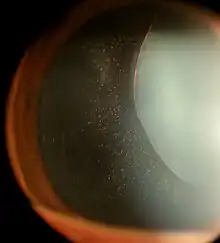

| Ectopia lentis in Marfan syndrome: Zonular fibers are seen. | |

In Marfan syndrome, the health of the eye can be affected in many ways, but the principal change is partial lens dislocation, where the lens is shifted out of its normal position.[17] This occurs because of weakness in the ciliary zonules, the connective tissue strands which suspend the lens within the eye. The mutations responsible for Marfan syndrome weaken the zonules and cause them to stretch. The inferior zonules are most frequently stretched resulting in the lens shifting upwards and outwards, but it can shift in other directions as well. Nearsightedness (myopia), and blurred vision are common due to connective tissue defects in the eye.[18] Farsightedness can also result particularly if the lens is highly subluxated. Subluxation (partial dislocation) of the lens can be detected clinically in about 60% of people with Marfan syndrome by the use of a slit-lamp biomicroscope.[18] If the lens subluxation is subtle, then imaging with high-resolution ultrasound biomicroscopy might be used.[19]